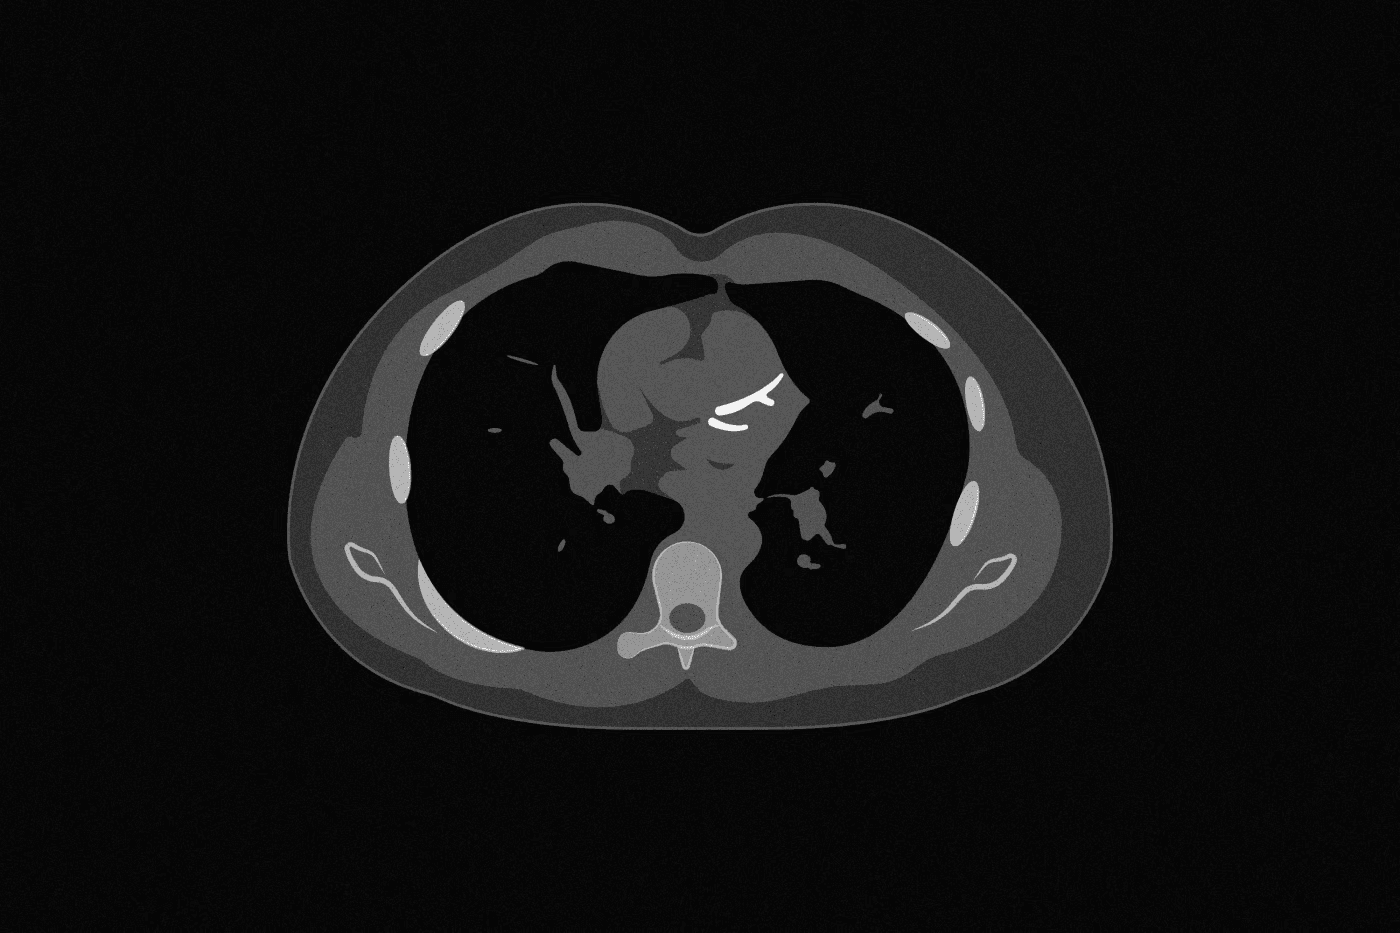

A calcium score is a quick 10 minute CT scan that answers the question: do you have calcified plaque in your heart arteries? It's more useful than blood tests and a zero is reassuring for most people over 55. But here's what most people don't know: it misses the soft plaque, which is the most important part.

A calcium score is a simple CT scan-based test that captures this solidified plaque. So a positive score is indicative of plaque presence in arteries.